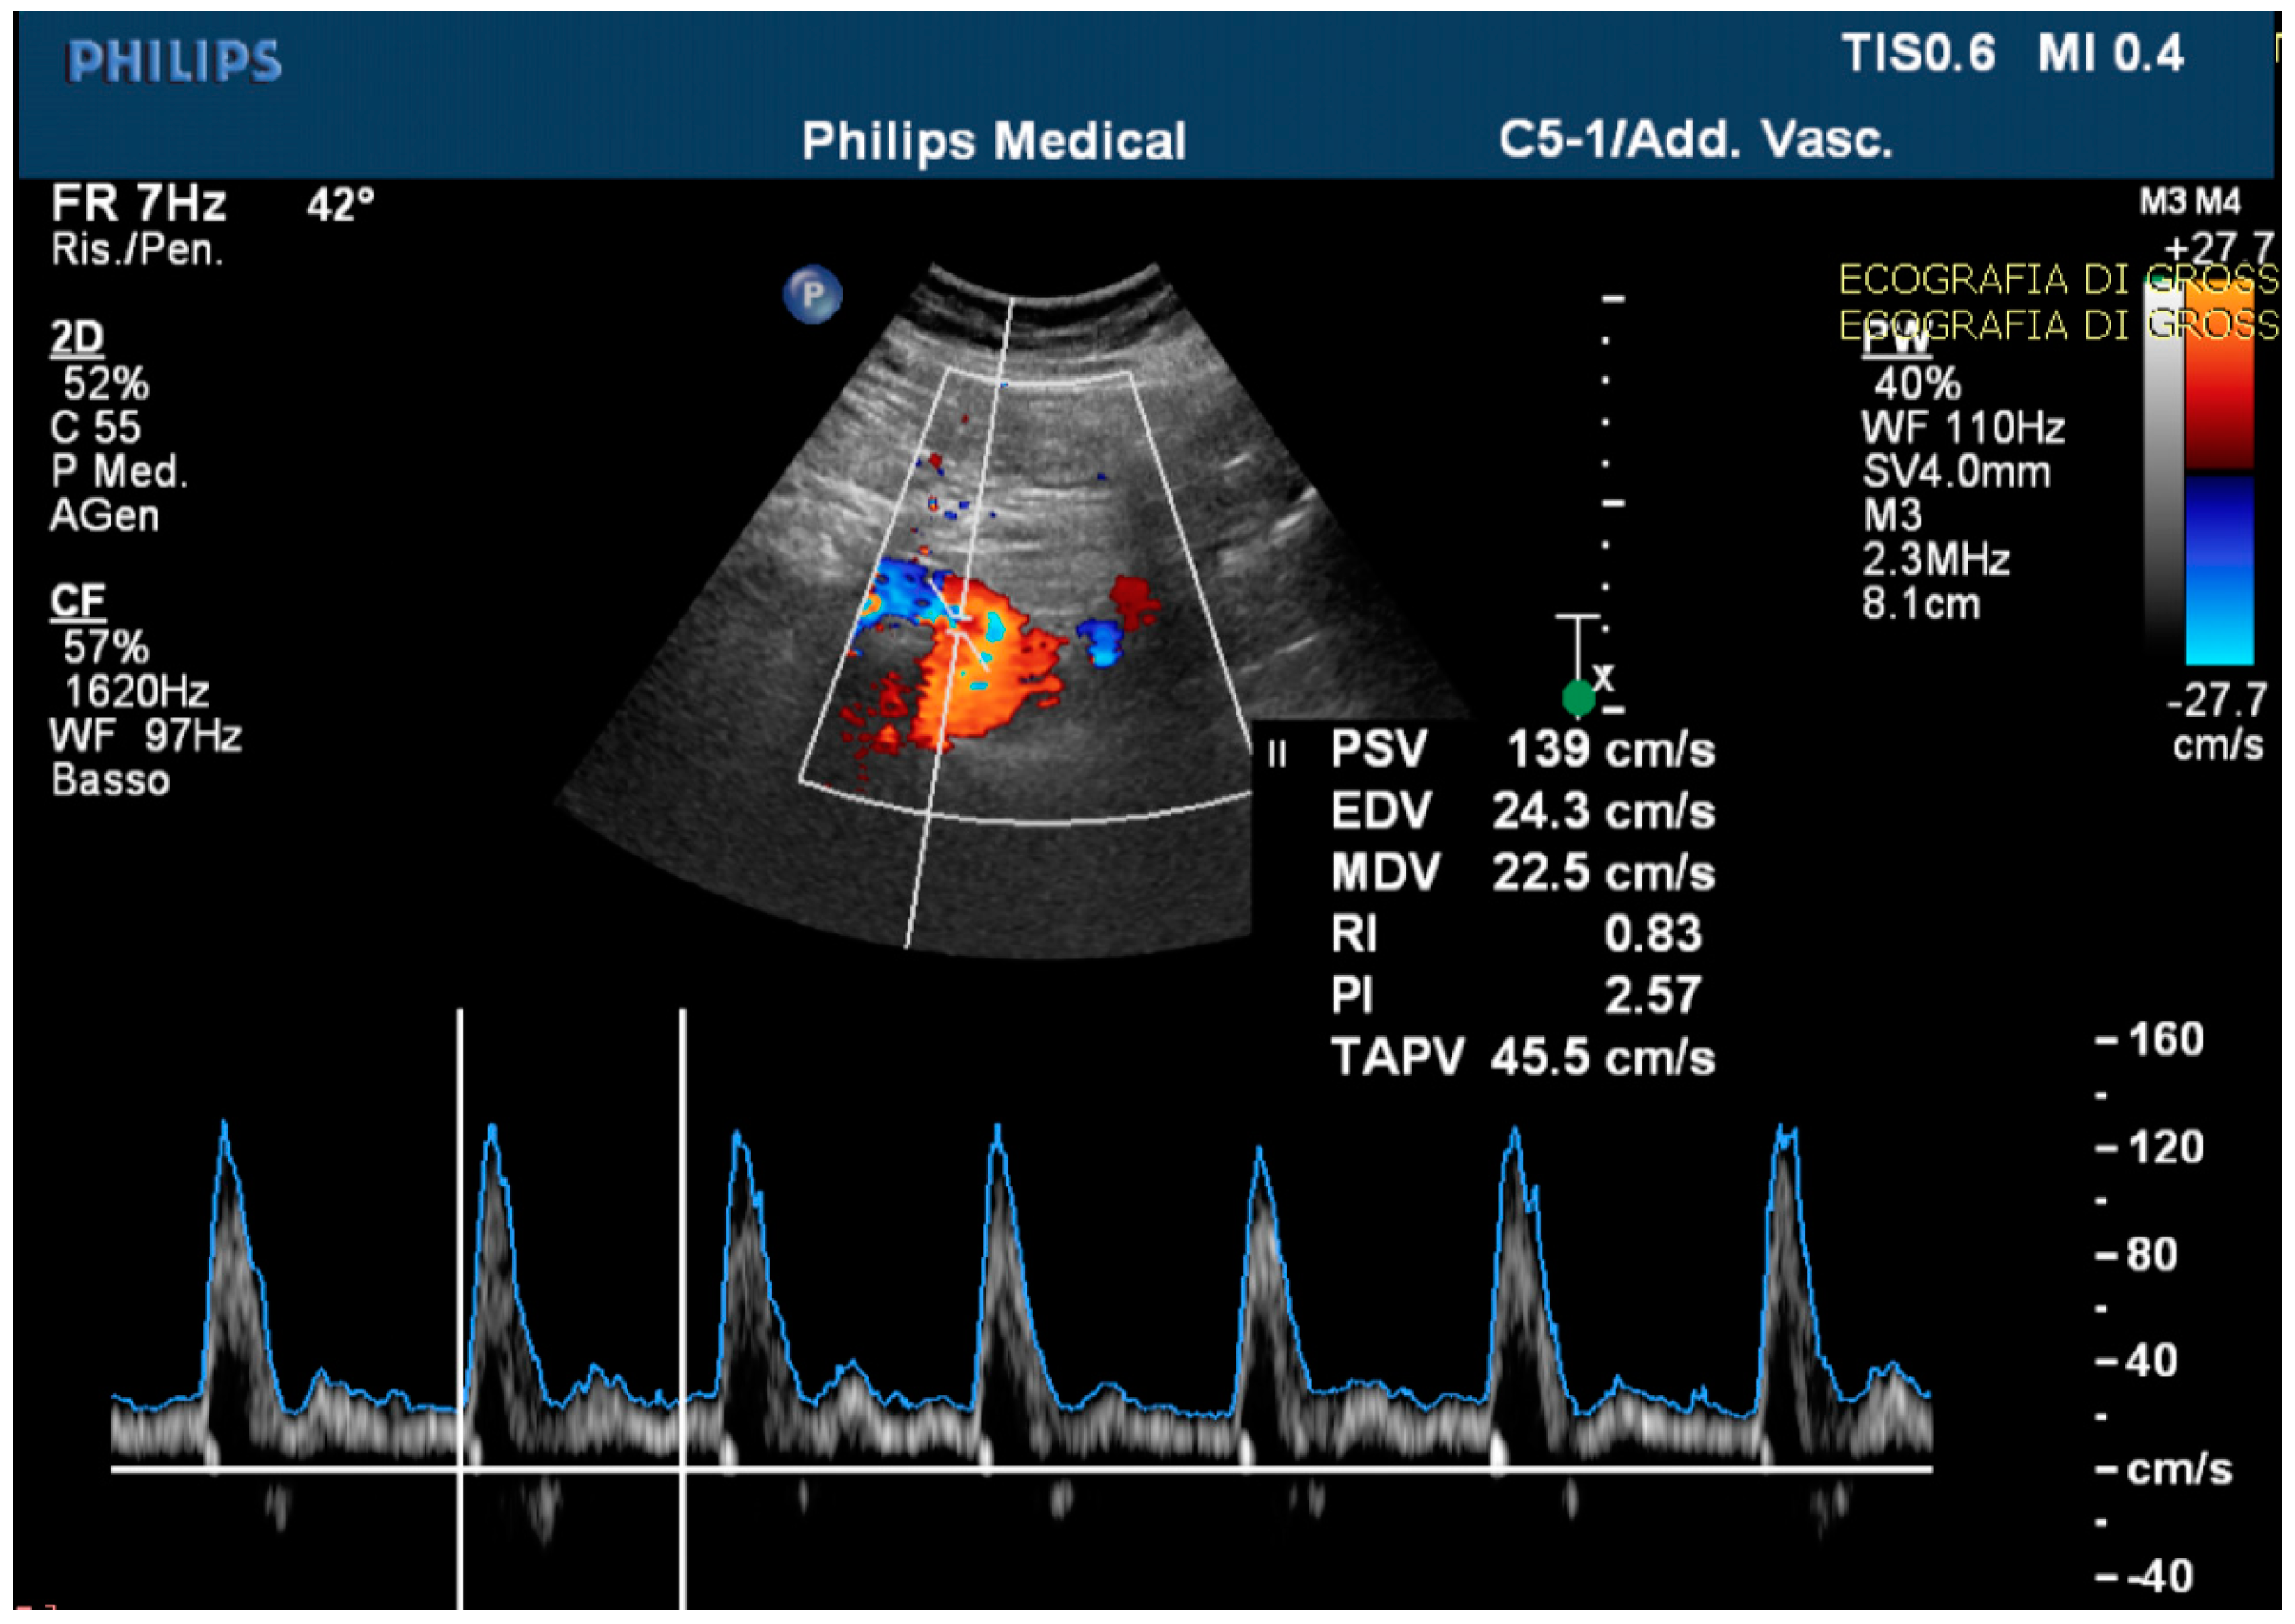

The echo-color-Doppler revealed a high resistance flow in the proximal site of the CMT (Figure 4).

Figure 4.

The echo-color-Doppler detected a high resistance flow in the proximal site of the celiac-mesenteric trunk, usually ranging from systolic velocity peaks between 90–100 cm/s (PSV); 30–65 cm/s end diastolic velocity peaks (EDV); and a pulsatility index (PI) of 1.5 ± 0.02.